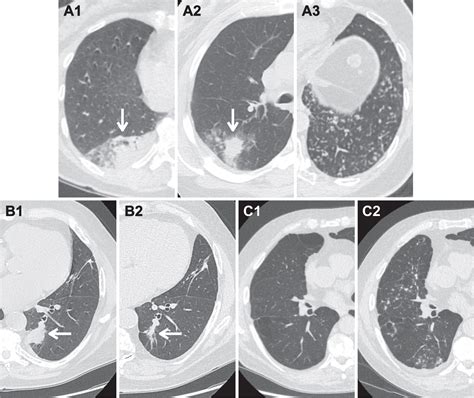

Diagnostic Criteria and Management Summary

The system relies on precise measurements of nodule diameter. Because solid and subsolid (ground-glass) nodules behave differently, the management recommendations in the Lung-RADS 2022 framework differentiate between these types. The following table provides a simplified overview of how findings are typically managed:

Lung-RADS Category Assessment Management Recommendation

Category 1 Negative Annual Screening

Category 2 Benign Annual Screening

Category 3 Probably Benign 6-month Follow-up CT

Category 4A Suspicious 3-month Follow-up CT or PET/CT

Category 4B/X Very Suspicious PET/CT, Biopsy, or Consultation